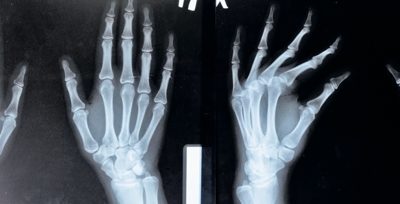

El riesgo de osteoporosis podría aumentar por la contaminación del aire

Una investigación dirigida por la Universidad de Columbia, en Estados Unidos, afirmó que la contaminación del aire podría incrementar el riesgo de desarrollar osteoporosis, enfermedad en la que los huesos se vuelven frágiles y más propensos a fracturas. Esto, señaló el estudio, podría deberse a gases como el óxido nitroso (N2O); además, el riesgo de pérdida ósea sería más alto en mujeres postmenopáusicas.